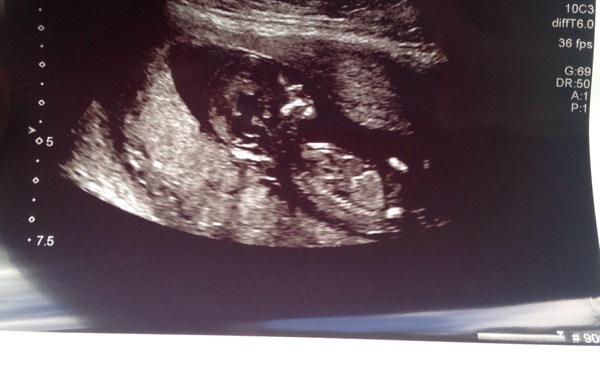

Heya. Sorry for being so quiet! Sickness has made me rather useless for a fair few weeks but it seems to be getting better now. My scan was today also :). My dates have been moved forward and am 13+1 with my DD being 26/12/2016

My scan also went well. Smile Sonographer had to jiggle my belly a bit to get the baby to turn over and uncurl but eventually it worked and we got a nice snap! NT was low so hoping for good blood results too. Due date is now 30th december!

Hey everyone. Sorry you guys are feeling so rough, I'm in the same boat as the sickness has been so bad this week. Scan went well. Confirmed I'm 12 weeks today & due date moved to 3rd Jan. I still think it'll be December but whatever happens it's out of my hands. Just got to get harmony results on Thursday. Reassuring to see the little bouncy baby.

Hi, I'm due 28 Dec, just had my scan and starting to really feel like it's real! My first baby so exciting and scary...nice to emeet everyone!